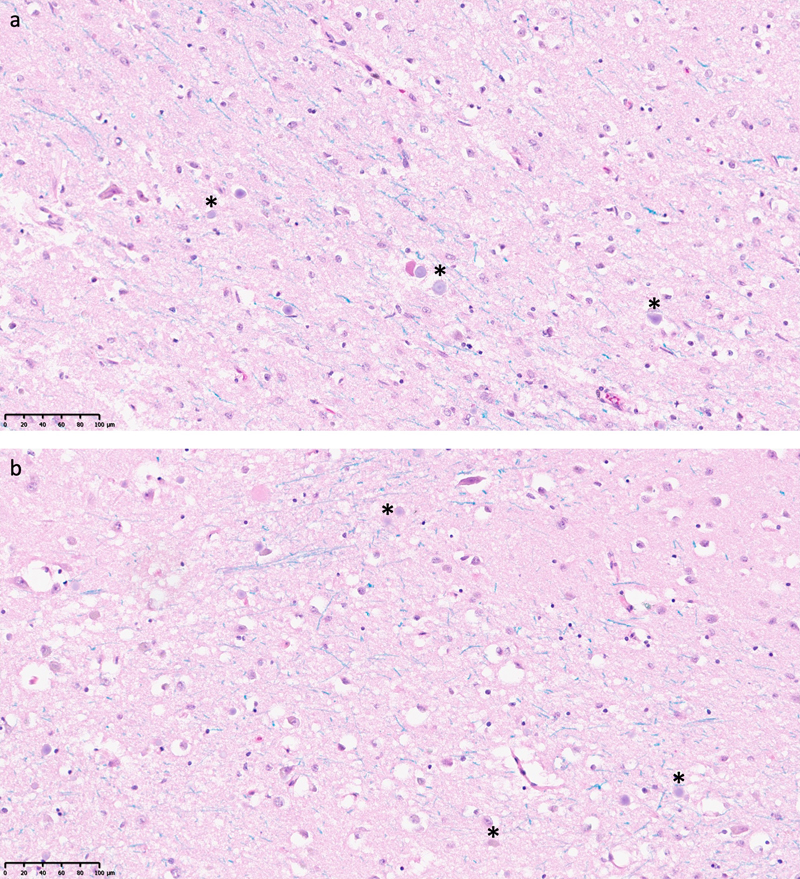

To evaluate for potential late-stage necrosis, two reviewers evaluated the presence of ghost cells in each of three gray matter regions of interest for all the WSIs available. Any given cell may have apparent characteristics of ghost cells, because of problems with staining or visualization, with a preponderance of these aspects at late-stage necrosis (Finnie et al., 2016). Out of the 321 regions of interest (ROIs) analyzed, we identified two ROIs that appeared to potentially have a substantially elevated number of ghost cells, although this may reflect differences in staining or imaging (Figure 2). These two ROIs with elevated numbers of ghost cells were found in samples from the posterior striatum, with PMIs of 53.5 h and 70.5 h. The tissue in these ROIs may represent areas that degraded especially rapidly for an unknown reason, or that may have been differentially affected by an artifact in the processing or imaging procedure. For the other two ROIs from these two samples, there was not a substantial number of ghost cells identified. Taken together, these observations indicate that the immersion fixation procedure generally maintained the histologic architecture on light microscopy as might be expected on a biopsy sample from autopsy brain tissue, with very few or no areas exhibiting substantial cellular necrosis.

Figure 2. Light microscopy of regions of interest showing a potentially significant number of ghost cells. The regions of interest were classified as having at least three potential ghost cells identified. Ghost cells are characterized by having absent or barely visible nuclei, pale-staining cytoplasm, and indistinct cell membrane morphology. Asterisks indicate cells potentially having these characteristics. It is unclear if staining or imaging factors could also contribute to this appearance. a: LHE-stained tissue section from the posterior striatum of a 62-year-old brain donor, with a PMI of 53.5 h. b: LHE-stained tissue section from the posterior striatum of a 76-year-old brain donor, with a PMI of 70.5 h. Scale bars: 100 μm.